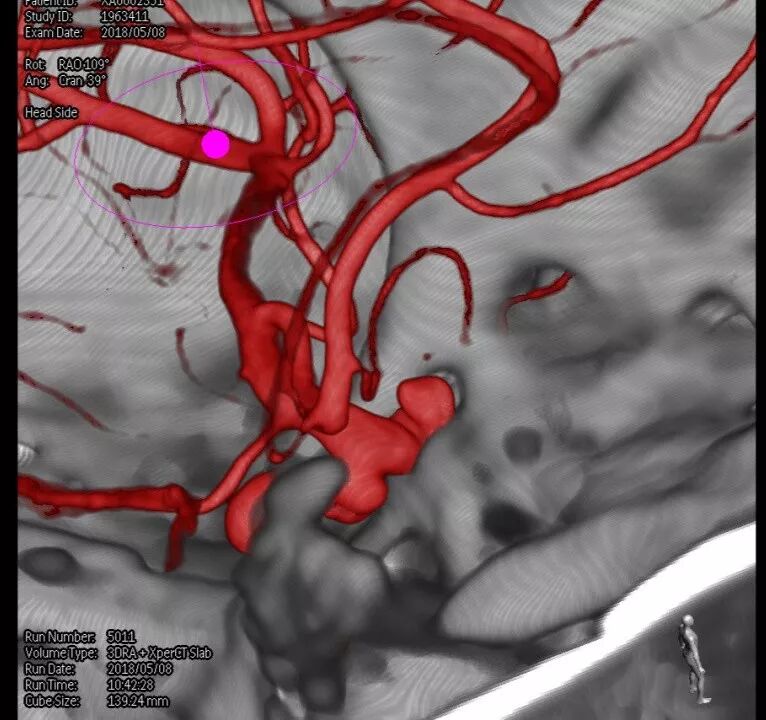

入院后完善DSA检查提示颅内多发动脉瘤:右侧颈内动脉眼段大动脉瘤(约18*19mm,瘤颈6.6mm),左侧眼动脉段及床突段动脉瘤。和家属沟通病情,告知介入和开颅手术风险利弊后,患者家属选择开颅动脉瘤夹闭手术治疗。进一步行DSA+CT融合,模拟手术入路视角。

术前科室讨论:根据患者术前DSA+CT融合图像,左侧动脉瘤因右侧巨大动脉瘤及骨性结构的遮挡,无法手术夹闭。拟先行右侧动脉瘤夹闭。但右侧动脉瘤体型巨大,位于眼段床突旁,临近颅底,术中需要磨除床突,但可能诱发瘤体破裂,若无法有效阻断血流,极可能出现致死性出血。可考虑术前暴露颈总动脉分叉部,术中临时夹阻断颈内动脉,但增加了手术创伤。建议利用复合手术室优势,术中介入球囊临时阻断颈内动脉后行动脉瘤夹闭。

结合本病例,我们术前利用复合手术室飞利浦DSA血管机,造影后即刻行CT扫描。由于是在同一机器环境下完成的两种模态扫描,减少了伪影干扰,解剖结构电脑自动吻合,故影像融合精度极高。并且因为是双模态融合,可以用不同颜色标记血管和骨窗,增加了对比度,提高了分辨率,较CTA有明显优势。利用术前融合模拟手术入路,放大后观察发现动脉瘤体巨大,紧贴颅底和床突,缺乏至少2mm的近端阻断空间,术中需要磨除前床突。但术中发现动脉瘤表面张力极高,紧贴床突硬脑膜,高速磨钻操作存在巨大风险。而术中球囊阻断颈内动脉后,动脉瘤张力明显下降,依靠吸引器轻轻牵拉即可暴露出瘤颈,不必要磨除床突,降低了手术复杂度。